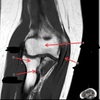

1

Not at all

2

3

4

5

Perfectly